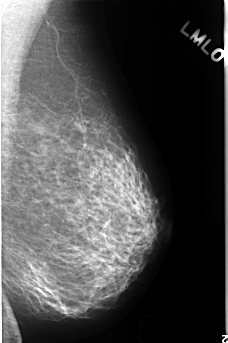

C_0384_1.LEFT_MLO

C_0384_1.LEFT_CC

LEFT_MLO LINES 4456 PIXELS_PER_LINE 2952 BITS_PER_PIXEL 12 RESOLUTION 50 NON_OVERLAY